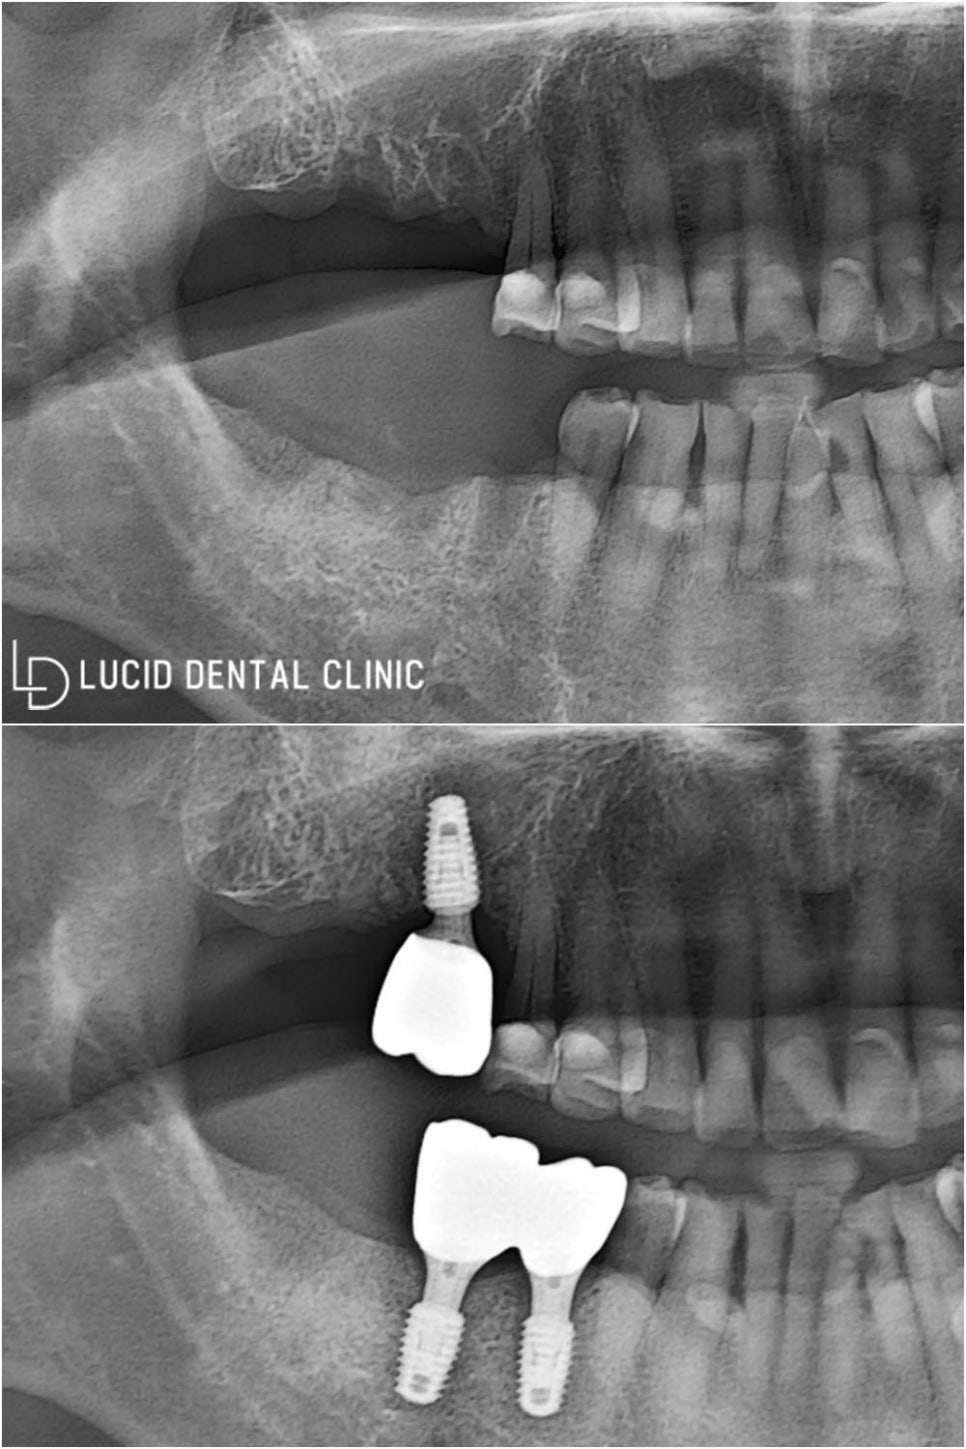

임플란트 치료 전/후 비교샷

환자께선 보철 체결 이후

식사가 이렇게 편할 수 없다며

크게 좋아하시곤 했는데요

나머지 왼쪽 부분도 치료하고 싶다며

다음 검진 일정을 예약하고 가셨습니다 ㅎㅎ